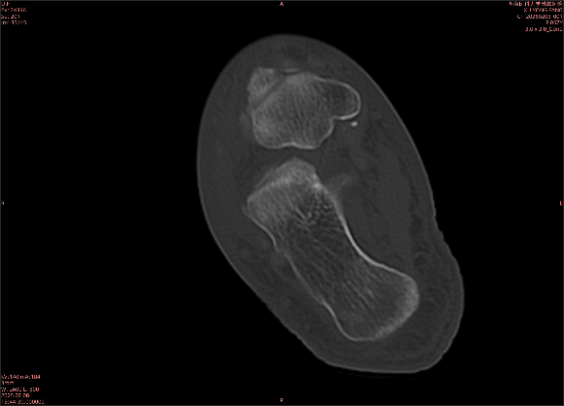

舉例圖像

圖1

專業(yè)解釋看不懂沒關(guān)系,大家看圖1和圖2就可以了,這是同一個患者跟骨的磁共振和CT圖像,圖1的紅色箭頭指示的黑線就是磁共振圖像顯示的骨折線,一目了然。而對比圖2的CT圖像上并未顯示異常。